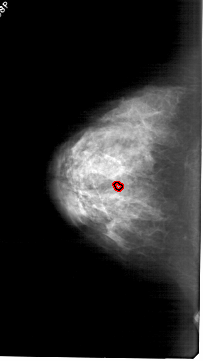

LEFT_CC LINES 6121 PIXELS_PER_LINE 3451 BITS_PER_PIXEL 12 RESOLUTION 43.5 OVERLAY